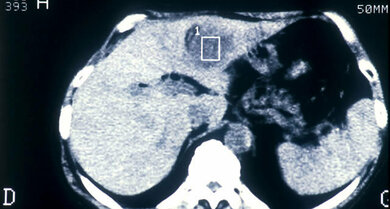

Im CT können Leberveränderungen sichtbar werden

© Mauritius/Alamy/BSIP

Besteht der Verdacht auf ein Leberzellkarzinom, tastet der Arzt zunächst den Bauch ab und betrachtet die Leber mittels Ultraschall (Sonografie). Die kontrastmittelverstärkte Ultraschalluntersuchung dient als Standardmethode unter den bildgebenden Verfahren, um ein Leberzellkarzinom zu diagnostizieren. Ergänzend kommen weitere bildgebende Verfahren unter Kontrastmittelgabe wie die Computertomografie (CT) und Magnetresonanztomografie (MRT) zum Einsatz. Mit oben genannten bildgebenden Verfahren unter Kontrastmittelgabe kann ein Leberkrebs meist eindeutig diagnostiziert werden. Sind aber die Bildbefunde auch nach mehrmaligem Einsatz nicht eindeutig, kann eine Gewebeprobe (Biopsie) Klarheit schaffen, zum Beispiel zur Diagnosesicherung bei kleineren Herden unter 2 cm Durchmesser. Zu einer Biopsie wird auch geraten, wenn vermutet wird, dass der Biopsiebefund die Wahl der Behandlung beeinflusst.

Nach Diagnosestellung eines Leberkrebses muss nun nach dessen Lage und Ausbreitung weitergesucht werden. Hierzu kommt erneut die Magnetresonanztomographie zur Anwendung, falls diese nicht bereits zur Diagnosefindung verwendet wurde. Hierdurch lässt sich die Anzahl der Tumorherde (meist finden sich mehrere Tumore in der Leber), die Lage der Tumore und ob diese schon in Blutgefäße oder umliegendes Gewebe eingewachsen sind bestimmen. Es handelt sich hierbei um das sogenannte intrahepatische Staging. Findet sich ein Gefäßeinbruch oder mehrere Herde in der Leber wird zur Beurteilung, ob sich bereits Tochtergeschwülste in andere Organe abesetzt haben (Fernmetastasen) ergänzend eine Computertomographie des Bauch- und Brustraums durchgeführt. Dies ist das sogenannte extrahepatische Staging.